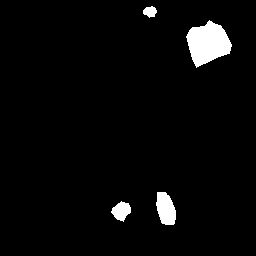

Figs. 2 and 3 present examples that illustrate the challenges of semantic segmentation methods. The trees in Fig. 2 show that in most images the foreground covers fewer pixels than the background (class imbalance). Besides, trees have edges that are difficult to label, and some pixels may be incorrectly labeled. Fig. 3 also illustrates the labeling challenge, in which some parts of the object are not visible in the image due to noise when capturing images.

Rib Eye Area (REA). This image dataset consists of ultrasound images of the Longissimus dorsi muscle between the 11th and 13th ribs of cattle. The goal is to automatically calculate the rib eye area (REA), an important region for decision making during cattle breeding. The main challenge is the uncertainty in the REA annotation, since the image is noisy and even experts have difficulty in delimiting the borders of this region. Fig. 3 presents examples of images and the annotation made by a specialist. We can observe that some borders are absent and depend on the subjectivity and knowledge of the annotator. To evaluate the segmentation methods, 76 images with resolution were obtained and labeled by an expert. Due to the number of images, the division of the images in training and testing followed 5-fold cross-validation.

REA dataset. This image dataset has high uncertainty during labeling due to noise from the ultrasound image. In some cases, the border of REA is not completely visible and must be estimated by the specialist. Therefore, the proposed approach becomes essential to obtain accurate segmentation at the edges. The segmentation examples in Fig. 6 show that the baseline was not able to define the REA correctly due to the uncertainty of the labeling. On the other hand, the proposed approach presents results close to the specialist in regions that the border needs to be estimated.